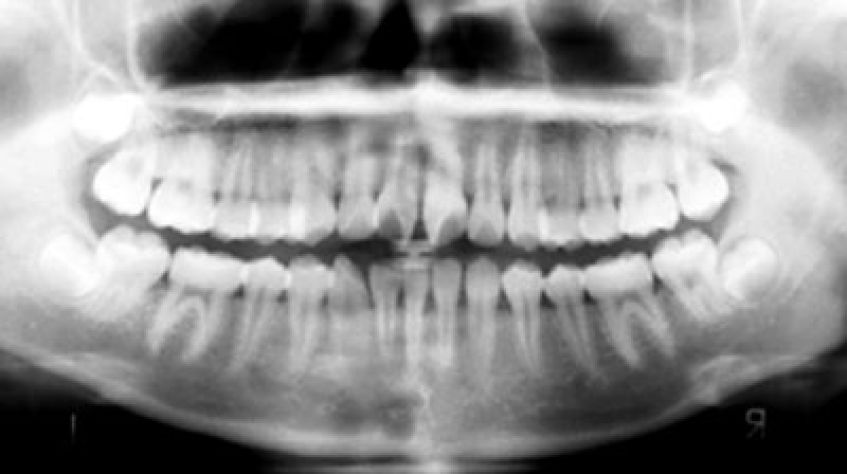

Что показывает панорамный снимок?

Панорамную съемку всей челюстной зоны, челюстных суставов и придаточных пазух носа позволяет осуществлять аппарат ортопантомограф. Такой снимок показывает врачу полную картину полости рта – от кариеса до изменения в костных тканях, дает возможность вовремя выявить воспаление на верхушках корней, даже когда нет иных сопутствующих симптомов. Панорамные снимки необходимы при ортодонтическом лечении, имплантации и протезировании зубов, а также в терапии при комплексном лечении заболеваний периодонта.

Использование панорамных снимков предусмотрено международными стандартами лечения, которые рекомендуют проводить подобное исследование ежегодно. Поэтому такой аппарат незаменим в работе современной стоматологической клиники.